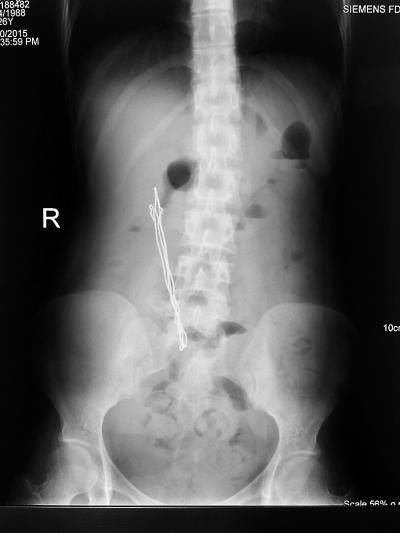

CT片显示铁丝斜插在林琳的腹中

医生经过检查,发现林琳腹腔内有一根15厘米长的金属异物。细长的异物斜插在肠子上,已经穿破了十二指肠,并在腹膜后形成了一根油条大的脓肿。而血液检查显示,林琳体内白细胞超标4倍多,提示存在严重的感染。

5月31日凌晨1点左右,医院普外科医生为林琳开始了取铁丝的手术。十二指肠在腹腔最深处,医生必须将十二指肠游离出来,找到破口,把异物抽出,因此只能选择剖腹。当暴露出林琳腹中的组织时,医生才看清楚,斜插在肠子上的是一根扭曲折叠的铁丝,长达15厘米,已经呈黑褐色了。